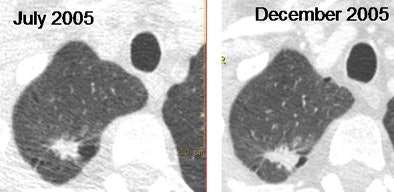

| Adenocarcinoma shows rapid growth over six months. Images courtesy of Dr. Mathias Prokop. |

Of the 372 detected nodules, 16 (4%) were malignant and 356 (96%) benign, the team reported. The baseline median CT density was 41.9 HU (range -195.1 to 192.1 HU) for benign nodules and -2.2 HU (range -127.5 to 75.0 HU) for malignant nodules (p = 0.06). The median density change for benign nodules was -0.2 HU (range -93.1 to 175.2 HU) and greater than12.8 HU (range -29.5 to 45.1 HU) for malignant nodules (p < 0.05).

"Of the 16 malignant nodules, there were eight adenocarcinomas, five squamous cell carcinomas, two large cell carcinomas, and one neuroendocrine carcinoma," she said. "An increase in nodule density at follow-up was found in eight cases."

While malignant solid nodules increased in density at follow-up, benign nodules did not show this change, suggesting that the density could be used in screening follow-up recommendations.